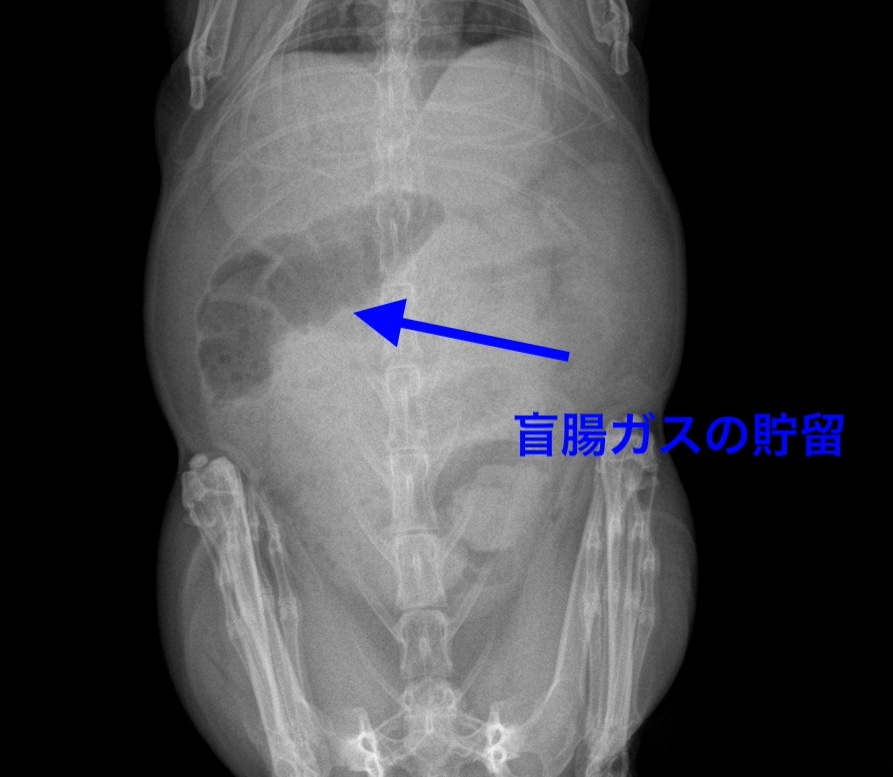

上記にも記載した通り、うさぎの盲腸は大きく、ガスが溜まるとレントゲンにて確認しやすくなります。

*レントゲンにて黒く見える部分が、盲腸のガスになります。